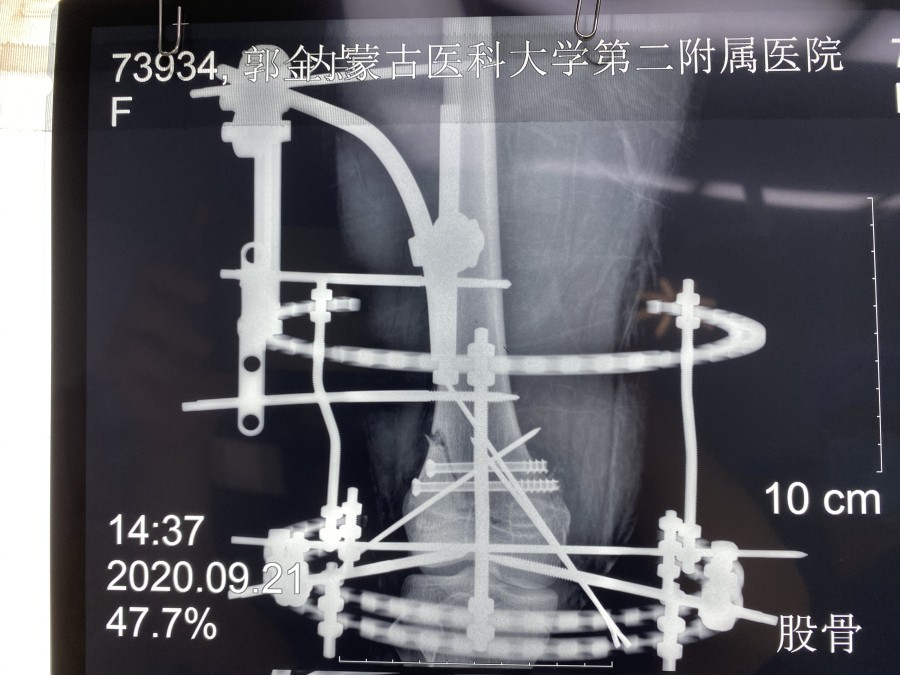

幸运的是MRI检查没有膝关节韧带和半月板的损伤。考虑到小郭的职业生涯,不能出现医源性肌肉等软组织损伤、以及运动员发达的大腿肌肉和术后快速康复的需求等等,小儿骨科团队进行了认真的术前讨论,9月21日,由韦宜山主任主刀实施了闭合复位经皮空心螺钉联合克氏针辅助Ilizarov环形外固定架手术治疗。手术非常成功,骨折端完全解剖复位,术后第1天小郭即开始床上膝关节主动和被动活动,第3天已可下地进行短时间不负重训炼,术后第10天已经可以独立扶双拐行走,10月9日,小郭顺利康复出院。术后,小郭一日三餐由91直播 营养部免费提供营养餐,病区护理人员专人负责陪护。